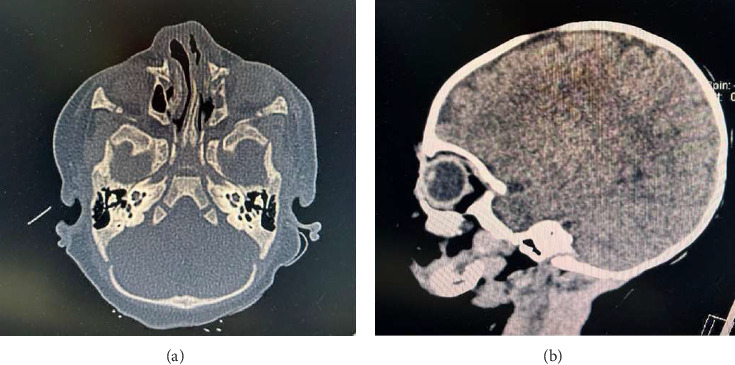

Congenital arhinia and hyporhinia are rare facial anomalies whose knowledge usually comes from case reports. The severity of each case described in literature is variable; it also depends on associated malformations too. Since the newborns are obligate nasal breathers, babies with arhinia or hyporhinia usually have respiratory distress and need airway stabilization. In addition, most of these children present difficulties in feeding and this impairment must be managed early. We describe an unusual case of partial congenital arhinia, the baby did not have other anomalies or any specific complication such as respiratory and feeding issues, so the major problem was the aesthetic and psychological issues for the family. Even if the neonatal course was uncomplicated, a coordinated approach of the pediatrician with the pediatric otolaryngologist, the geneticists and the neurosurgeons was necessary because the management of these malformations is always very complex; due to the lack of reports described in literature, an univocal management and also the best timing and technique for reconstructive surgery are still not defined.